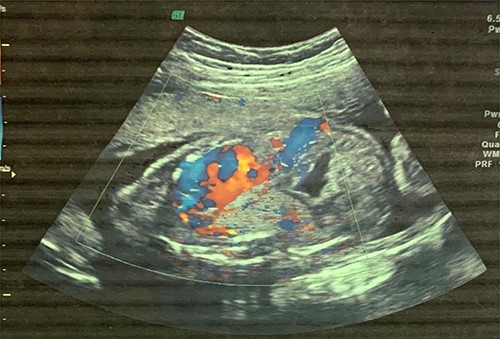

A 6-month-old male baby who was found to have fetal adenomatoid malformation from a prenatal ultrasound (US) done at 20 weeks’ gestation and polyhydramnios at 30 weeks’ gestation (Fig. 1) is reported. The mass measured 4.7 × 4.1 × 3.5 cm with no evidence of systemic feeding artery, associated anomalies or hydrops at 24 weeks. Cesarean delivery was done at 38 weeks’ gestation for severe polyhydramnios. He spent first 3 weeks at the neonatology unit with respiratory distress and again on sixth week of life for pneumonia. A chest computed tomography (CT) scan (Fig. 2) at 2 weeks showed a wedge-shaped homogenously enhancing mass measuring 4.8 × 2.8 × 1.8 cm in the left lower lobe with an aberrant arterial branch from the descending thoracic at T12. Cardiothoracic surgery reviewed and maintained patient for surgery. He had normal preoperative laboratory work-up and underwent aberrant artery ligation and resection of the sequestrated lung via standard left posterolateral thoracotomy.

CT scan images depicting intralobar pulmonary sequestration of the left lower lung lobe.